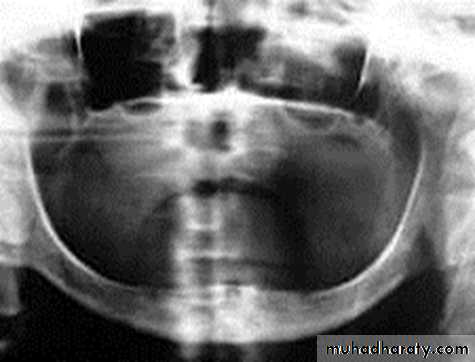

Epiosteal / Subperiosteal Implants

They placed directly beneath the periosteum overliying the bony cortex (not anchored inside the bone)Receive primary bone support by resting on it.

Disadvantages :

1) Slow, predictable rejection of the implant

2) Bone loss associated with failure

• Usually indicated in a severely resorbed, completely edentulous mandible which does not offer enough bone height to accommodate root form implants as anchoring devices.